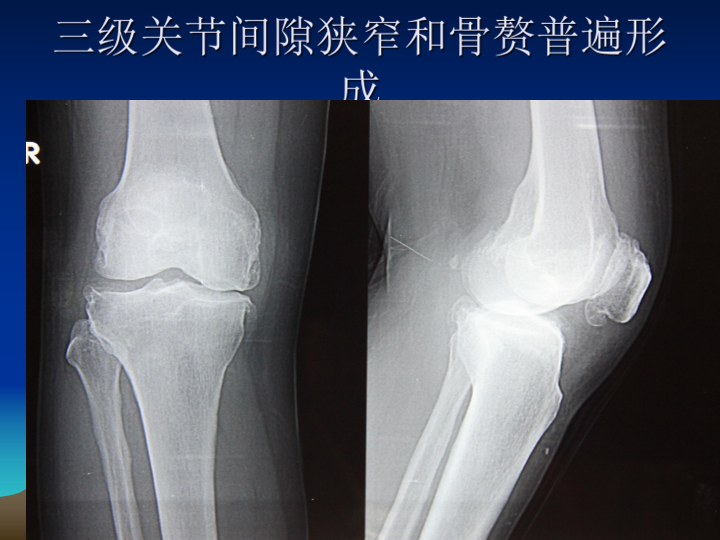

膝关节骨性关节炎阶梯治疗